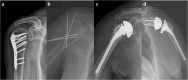

This study protocol was exempted for review by the institutional review board of the Hanyang University Hospital (HYUH 2017–08-023) in accordance with the exemption criteria. Informed consent was exempted because this study used only data opened to the public. The plain radiographs demonstrating types of surgical treatment of proximal humeral fractures were included in Fig. 1 after receiving written informed consent from the patients.

Consent was obtained from patients whose images are presented in Fig. 1.